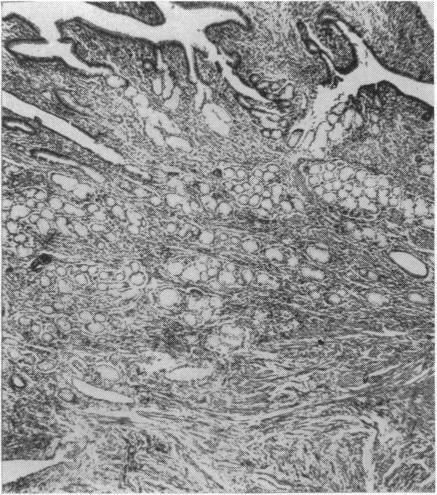

Crohn's disease of the large bowel has been increasingly recognized and this paper presents a clinical and pathological study of 45 patients in whom the disorder was confined entirely to the large intestine. The clinical and pathological factors are contrasted with those of 86 patients with regional ileitis and of 200 patients with ulcerative colitis. Compared with regional ileitis the disease occurred in an older age group, had a different sex distribution, and a higher incidence of perianal and rectovaginal fistulae. A high incidence of recurrent disease following surgical treatment, found in the patients with regional ileitis, was not found in the patients with primary Crohn's disease of the large intestine. The incidence of the disease relative to ulcerative colitis was approximately 6%. The disease had the same sex distribution as ulcerative colitis but occurred in an older age group. The disease was usually of gradual onset and continuous course, and periods of freedom lasting a month or more were uncommon. The patients came to surgery much earlier than patients with ulcerative colitis.

大肠克罗恩病已越来越受到人们的认识,本文对45例病变完全局限于大肠的患者进行了临床和病理研究。将这些患者的临床和病理因素与86例局限性回肠炎患者及200例溃疡性结肠炎患者的因素进行了对比。与局限性回肠炎相比,该病发生于年龄较大的人群,性别分布不同,肛周和直肠阴道瘘的发生率较高。局限性回肠炎患者手术治疗后复发率较高,而原发性大肠克罗恩病患者未发现这一情况。相对于溃疡性结肠炎,该病的发病率约为6%。该病的性别分布与溃疡性结肠炎相同,但发病年龄较大。该病通常起病隐匿、病程持续,持续一个月或更长时间的缓解期并不常见。这些患者比溃疡性结肠炎患者更早接受手术治疗。